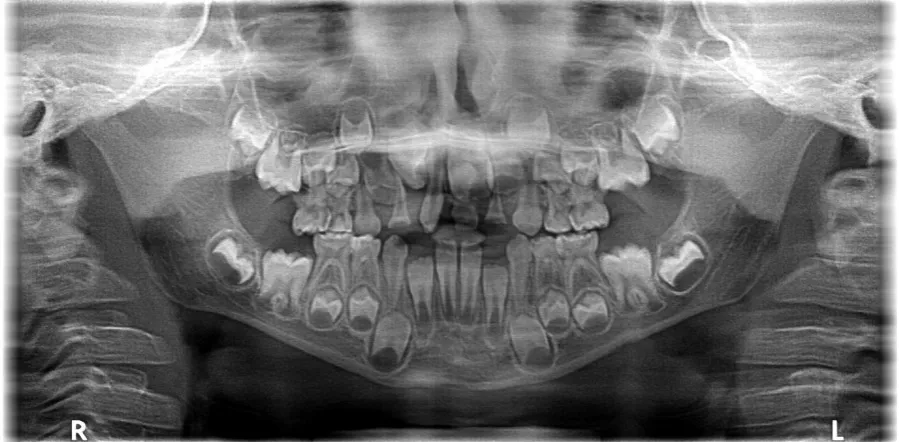

Zmiana liczby zębów jest naturalnym procesem rozwojowym, który zaczyna się u dzieci i trwa przez wiele lat. Wymiana uzębienia z mlecznego na stałe rozpoczyna się zazwyczaj około 6. roku życia i jest kontynuowana do około 12-13. roku życia. Mechanizm ten jest fascynujący: pod naciskiem wyrzynających się zębów stałych dochodzi do resorpcji, czyli stopniowego zaniku korzeni zębów mlecznych. To sprawia, że zęby mleczne stają się ruchome i w końcu wypadają, ustępując miejsca swoim stałym następcom. Jako stomatolog, zawsze podkreślam rodzicom, jak ważna jest dbałość o mleczaki, ponieważ ich przedwczesna utrata może wpłynąć na prawidłowe wyrzynanie się zębów stałych.

Uzębienie mleczne, choć tymczasowe, odgrywa niezwykle ważną rolę w rozwoju dziecka nie tylko w procesie żucia, ale także w prawidłowym rozwoju mowy i kształtowaniu się kości szczęk. Dziecko posiada łącznie 20 zębów mlecznych: 10 w szczęce górnej i 10 w żuchwie. W skład tego zestawu wchodzi 8 siekaczy (po cztery w każdej szczęce), 4 kły (po dwa w każdej szczęce) oraz 8 zębów trzonowych (po cztery w każdej szczęce). Co ciekawe, w uzębieniu mlecznym nie występują zęby przedtrzonowe pojawiają się one dopiero w uzębieniu stałym, zastępując trzonowce mleczne.

Kiedy mówimy o uzębieniu stałym, często pojawia się pytanie o dokładną liczbę zębów. Jak już wspomniałem, u dorosłego człowieka liczba ta wynosi od 28 do 32 zębów. Ta różnica wynika z obecności tak zwanych zębów mądrości, czyli trzecich trzonowców. Osoby, u których wszystkie cztery ósemki prawidłowo się wyrżnęły, mogą cieszyć się pełnym kompletem 32 zębów. Natomiast u tych, u których zęby mądrości nie wyrosły wcale, zostały usunięte lub występują w mniejszej liczbie, uzębienie stałe będzie liczyło 28, 29, 30 lub 31 zębów. To bardzo indywidualna kwestia, którą zawsze sprawdzam podczas rutynowych kontroli.

Choć standardowo mówimy o 20 zębach mlecznych i 28-32 stałych, natura czasem płata figle, prowadząc do anomalii w liczbie zębów. Jedną z nich jest hiperdoncja, czyli występowanie zębów nadliczbowych. Oznacza to, że w jamie ustnej pojawia się więcej zębów niż standardowe 20 u dzieci lub 32 u dorosłych. Jest to, co ciekawe, druga najczęstsza wada zębowa. Najczęściej spotykanym zębem nadliczbowym jest tak zwany mezjodens, który wyrasta między górnymi jedynkami. Zęby nadliczbowe mogą powodować problemy z estetyką, ortodoncją oraz prawidłowym wyrzynaniem się innych zębów, dlatego ich wczesne wykrycie jest kluczowe.

Na drugim końcu spektrum anomalii znajduje się hipodoncja. Jest to wrodzony brak zawiązków jednego lub więcej zębów, co skutkuje ich zmniejszoną liczbą w jamie ustnej. Hipodoncja może dotyczyć zarówno zębów mlecznych, jak i stałych, choć częściej obserwujemy ją w uzębieniu stałym. Najczęściej brakuje zawiązków drugich siekaczy bocznych, drugich przedtrzonowców czy zębów mądrości. W zależności od stopnia nasilenia, hipodoncja może prowadzić do problemów z żuciem, mową, estetyką uśmiechu oraz stabilnością zgryzu. W takich przypadkach często konieczne jest leczenie ortodontyczne połączone z protetycznym uzupełnieniem brakujących zębów.